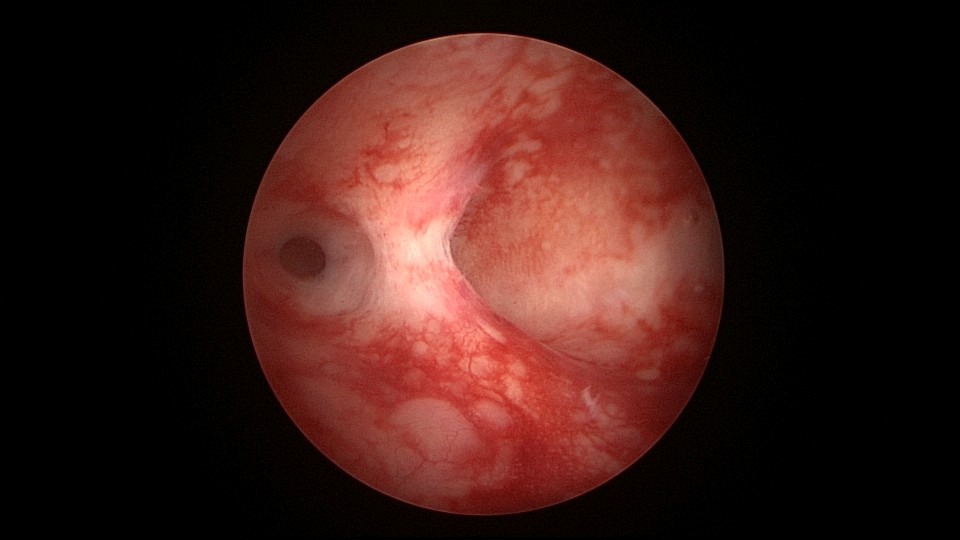

患者42,G3P1,顺产1次。子宫腺肌症伴腺肌瘤,逐渐加重的痛经,2024年11月起皮下注射亮丙瑞林3个周期,出现潮热出汗症状。2025年4月,要求放置曼月乐环并固定,子宫后位,宫深9cm,宫腔上段右侧粘连,宫腔下段宽大。4-0不可吸收线将曼月乐缝合固定于宫腔上段后壁,缝线上靠近曼月乐间距1cm左右打3个结,缝合1针,将1个线结拉过缝合处肌层,利用子宫肌层线结卡压固定曼月乐,避免打结推结。术后多次复查B超,曼月乐位置正常,环顶端距宫底1.6cm。